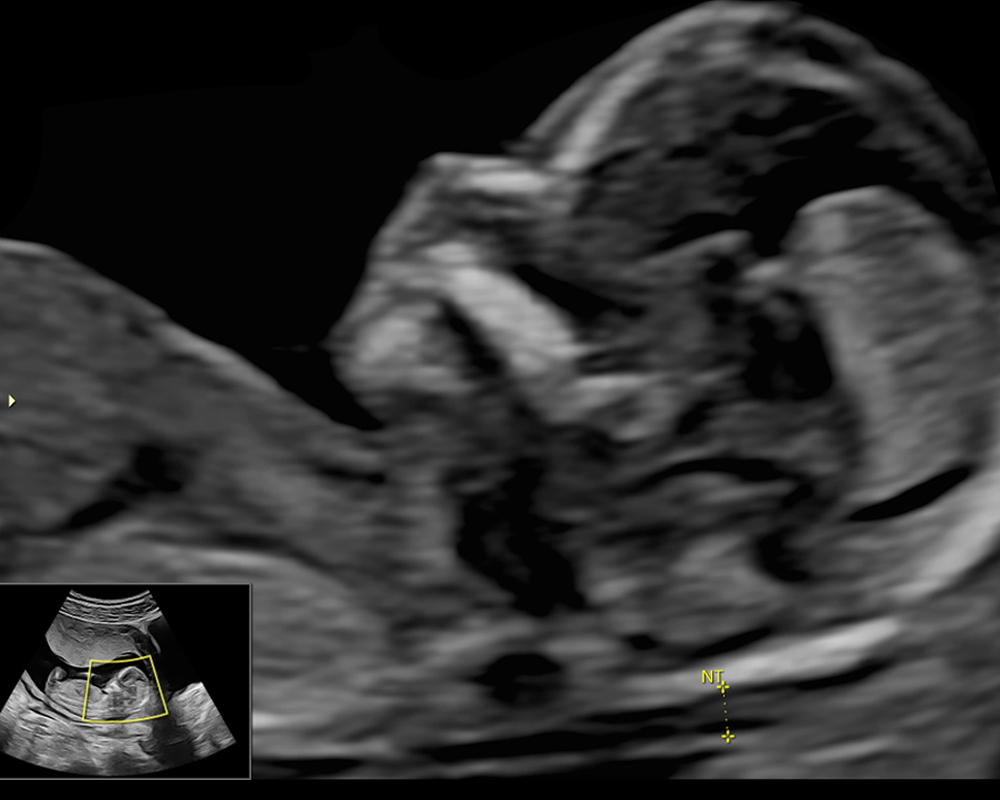

Ecografía Genética: Eco del Primer Trimestre

La ecografía genética, también llamada eco genético o ultrasonido genético, el cual se realiza entre las semanas 11 y 14, es fundamental para el diagnóstico precoz de enfermedades genéticas, como el Síndrome de Down. Además de ofrecer una ventana temprana acerca de la salud genética de bebé, con esta ecografía podemos estimar el riesgo de presentar preeclampsia en el embarazo. Esta última condición puede ser prevenible y evitar que complique la salud de mamá y bebé.